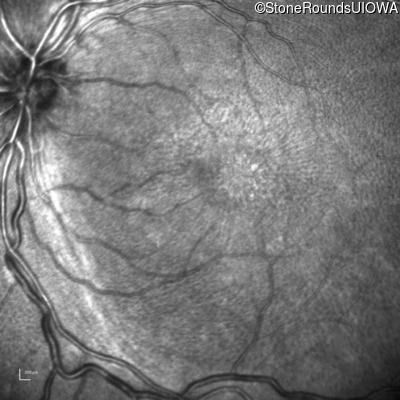

XL Retinoschisis (IIIB1)

Age at visit: 6 years

This 6 year old boy began sitting very close to the television at age 2.

Diagnosis & molecular findings

XL Retinoschisis RS1 Tyr93Stop TAT>TAG   XL